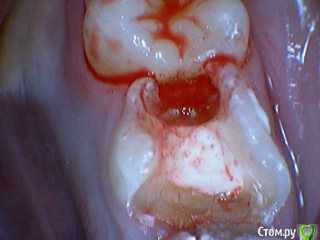

Давлетшин Опубликовано 29 декабря, 2017 Поделиться Опубликовано 29 декабря, 2017 (изменено) Друзья. Расскажите, не поменялось ли ваше отношение к пульпотеку и пр.Почему пломбы поверх пульпотеку такие ужасно жёлтые? Что сделать можно. Или что я делаю не так? "Друзья" так приятно перед новым годом. К пульпотеку не поменялось (устраивает вполне) , к пульподенту скептическое отношение, хоть и тоже работаю. Пломбы сразу желтые или через полгода - год- два? Очень тяжело что то советовать он лайн не видя как человек работает. В фото первая цифра пациент, вторая-третья номер зуба, четвертая порядок фото. Я после наложения пульпотека , стараюсь убрать излишки, или аккуратно на устья каналов накладываю, в пульповую камеру СИЦ, и сверху пломбу, Убрать излишки и со стенок, аккуратно в том числе и бором. В третьем клиническом случае, неудача. Зуб удалил сам же через 3 месяца. причину вижу в том что на рентгене не увидел (или так сделали снимок?) вертикальный тип рассасывания практически до бифуркации., может и потому что ребенок ОЧЕНЬ плохо сидел. За фото не пинайте сильно, не инстаграмм все таки,да и тяжело ребенка лечить и фотки делать. или наоборот пинайте может лучше начнем фоткать. P.s. Добавлю протокол как лечу с пульпотеком, хр.фибр.пульпит1. анестезия2. кофер ( если дает)3. раскрытие кариозной и пульповой камеры4. удаление коронковой пульпы маленьким эскаватором, я стараюсь "отрубать" пульпу5. остановка кровотечения сухим ватным шариком, 0,5-1-2 минуты6. пульпотек на устья7 СИЦ в пульповую камеру8 со стенок остатки пульпотека соскребаю бором фиссурным , цилиндрическим, там же фальц9. Пломба. может что то и зыбыл ну и оценка только позитивная перед НГ Изменено 29 декабря, 2017 пользователем Давлетшин 2 Ссылка на комментарий